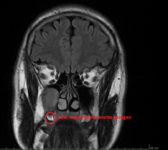

Weil ich Angst habe das mein Hirn von Schwermetalle geschädigt ist, und die Radiologie es nicht sieht ( weil die Microweiße Punkte im Hirn keiner Bedeutung zuweisen, diese sich aber über kurz oder Lang vergrößern können) habe ich die CD's der beiden MRT's aus den letzten beiden Jahren angefordert und möchte mittels Daunderers Bildmaterial mein Hirn mal vergleichen. Vielleicht erkenne ich ja Auffälligkeiten.